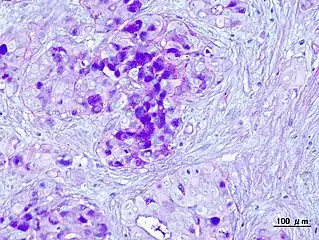

Micrograph of a mucoepidermoid carcinoma. FNA specimen. Pap stain.

In terms of diagnosis we find that histological staining, radiological imaging and molecular diagnostic features all play a role in the evaluation[1] This tumor is not encapsulated and is characterized by squamous cells, mucus-secreting cells, and intermediate cells.[7]